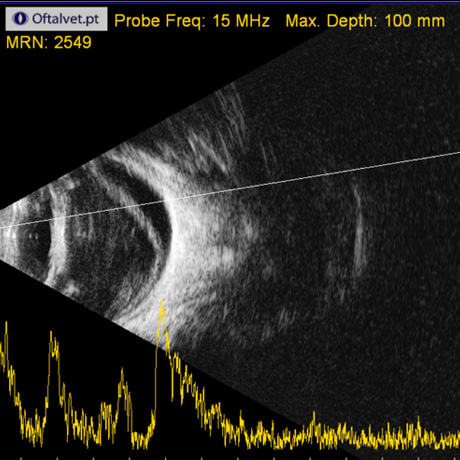

Na Oftalvet dispomos de equipamento avançado, de última geração, que permitem o diagnóstico das mais variadas doenças que afectam o globo ocular e seus anexos.